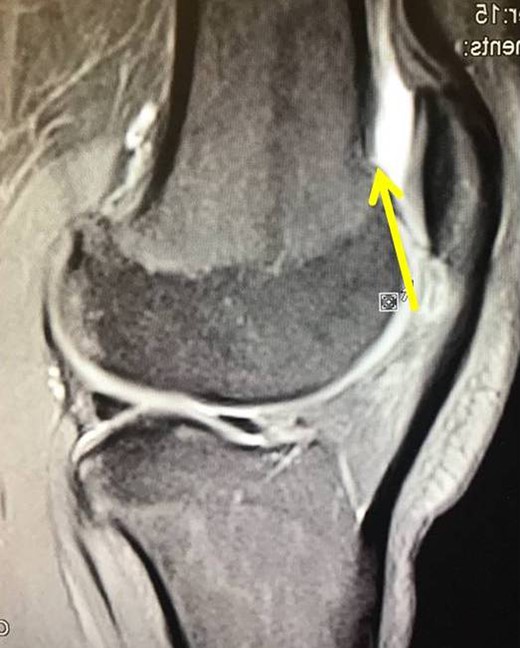

The second case involved an 18 years old male with pain and swelling at the anterior surface of the left knee, under the rectus femoris muscle over the patella. Symptoms exacerbated during knee bending over 90 degrees. X-rays and MRI revealed an extra-articular exostosis, just over the suprapatellar pouch (Figs. 3A and B). Under general anesthesia, a standard antero-lateral portal was used to access the knee arthroscopically. The capsule of the suprapatellar pouch was divided providing access to the adjacent extra-articular osteochondroma. Through a medial, a far supero-medial and supero-lateral portal, the exostosis resected by using an osteotome and removed with a grasper through the supero-lateral portal. The lesion had maximum dimensions 3.1 × 1.4 cm and its histopathological examination set the diagnosis of osteochondroma. Postoperatively, the patient was pain free with full range of knee motion. No recurrence was observed at 9 months (Fig. 4).

(A) X-ray of the exostosis in the second patient, (B) MRI depicts the lesion.